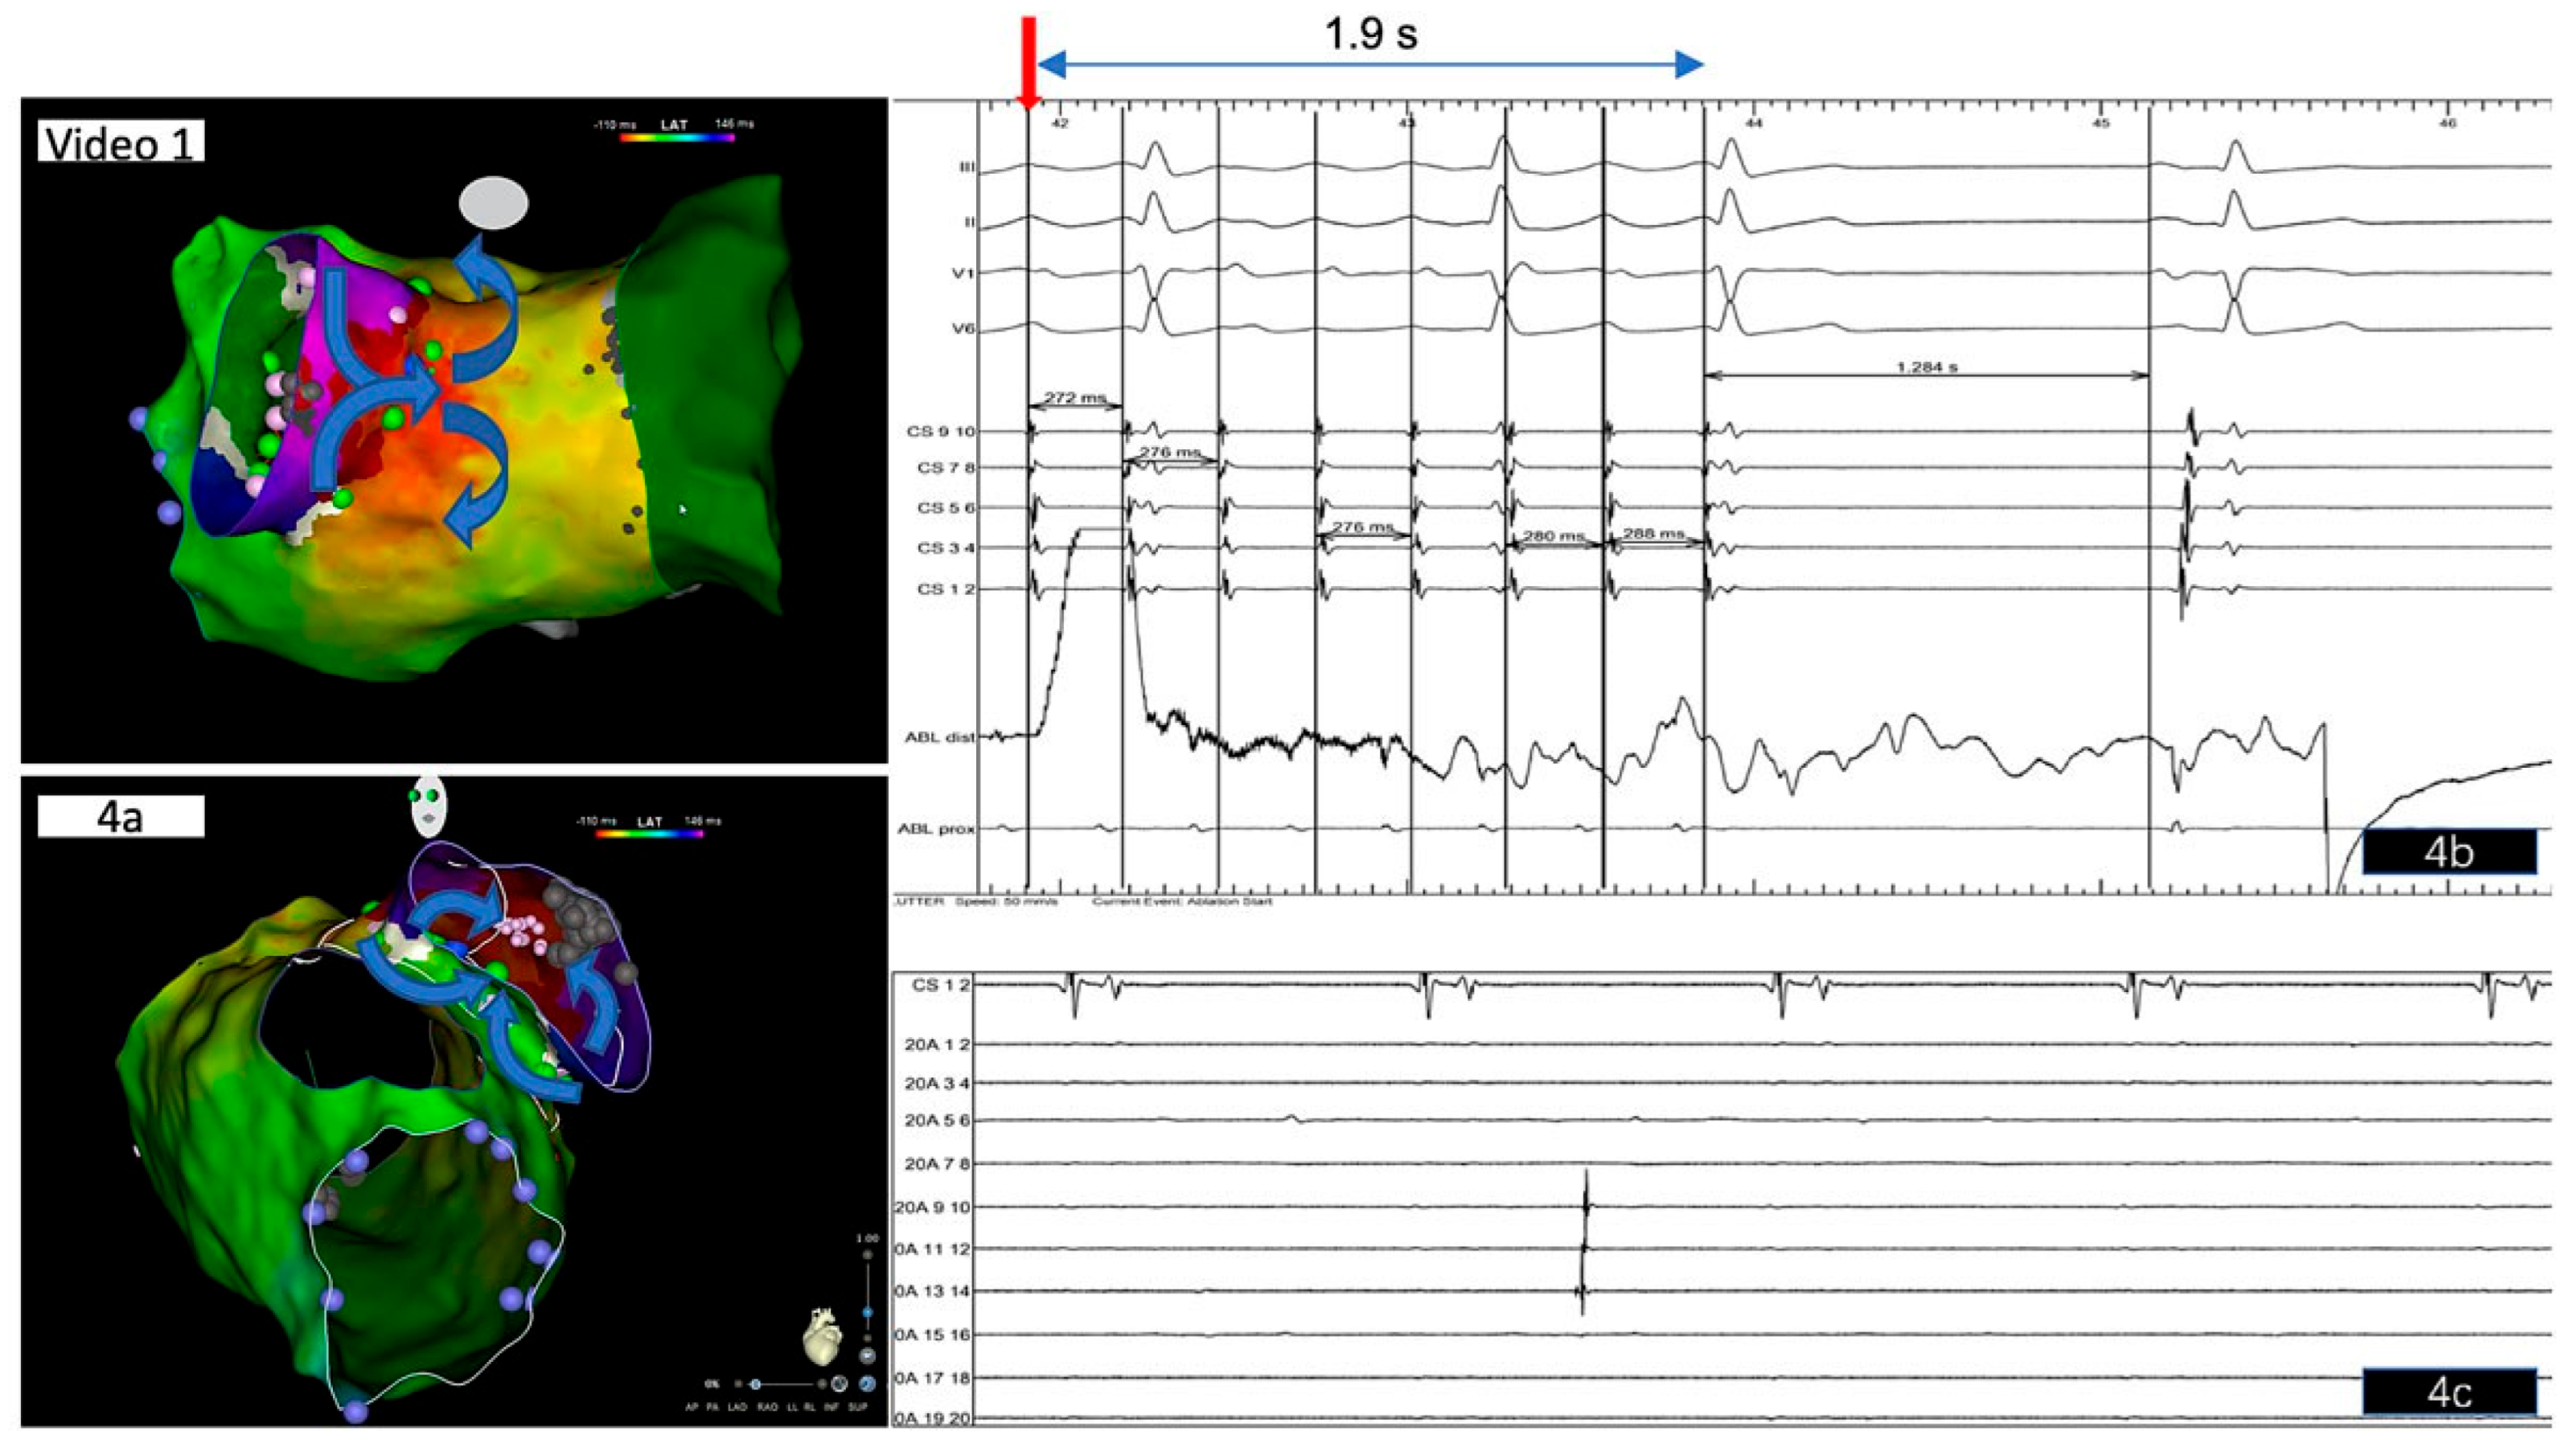

Case description

Electrophysiological study and ablation